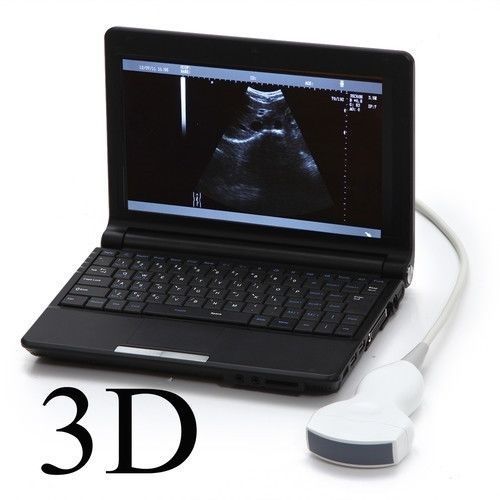

Laptop Ultrasound Scanner +Transvaginal Probes 3.5MHz Micro Convex Probes SALE !